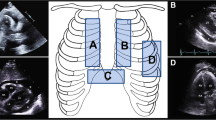

The pericardium, a fibroserous sac surrounding the heart, plays a crucial role in protecting and maintaining cardiac function. The serous visceral pericardium is adherent to the surface of the heart, and the fibrous parietal pericardium is loosely applied over it. This creates a virtual space between the two layers. The pericardial layers surround the cardiac chambers and blend with the adventitial layer of the great vessels at the base of the heart superiorly and with the central tendon within the diaphragm inferiorly. Physiologically, the space between the two layers, i.e., the pericardial sac, is small and normally contains 15 to 20 cc of fluid, which acts as a lubricant and minimizes friction between the two layers [1]. Except for the small spaces that exist along the pericardial recesses formed by reflections of the pericardium, elsewhere these two layers appear as one on imaging (Fig. 1A).

Axial CT images of the chest. A Normal pericardium, with the two layers of pericardium abutting one another and seen as a single layer (white arrow). B Pathological accumulation of fluid in the pericardial cavity separating the visceral (red line) and parietal (blue line) layers of the pericardium. Internal mammary vessels (interrupted white arrows) identified here should be avoided during pericardiocentesis

Pericardial effusion is defined as a greater than normal volume of fluid in the pericardial space. With pathological accumulation of fluid, the two pericardial layers are separated by the increase in the amount of collection in the pericardial space (Fig. 1B). The clinical significance of pericardial effusion is characterized by the effect it has on the diastolic filling of the cardiac chambers, particularly the right atrium and the right ventricle. Pericardial effusion may be classified based on the rate of fluid accumulation (slow vs rapid), the pattern of distribution around the cardiac chambers (localized vs. circumferential), the hemodynamic effect it has at the time of diagnosis (asymptomatic, mild-to-moderate symptoms, or tamponade), and its composition (transudative, exudative, hemorrhagic, or chylous).

Echocardiography-guided pericardiocentesis is often performed through a left parasternal or subxiphoid access. Overlying lung can preclude the operator’s ability to choose a more lateral intercostal approach to drain a posterior pericardial effusion. CT guidance, however, offers additional access options to reach the pericardial space, as the distribution and nature of the pericardial effusion can be easily assessed on CT. Klein et al. [15] and Davit et al. [16] reported that approximately 25 to 46% of CT-guided accesses in their patients were through the intercostal space, 12 to 26% were through a right parasternal approach, and 15% were through a left subcostal approach. In parasternal approach, there is a risk of injury to internal mammary arteries; CT images can be used to locate (Fig. 1B) and plan a needle trajectory that can avoid these vessels. While using an intercostal approach, it is important to stay just above a rib, to avoid injury to intercostal arteries. CT is also of use for loculated pericardial effusions. When the effusion is loculated, especially in the postoperative setting, CT imaging allows precise evaluation of any residual pericardial fluid after initial pericardiocentesis and can assist in the drainage of additional loculations to achieve adequate symptom relief. CT imaging also allows operators to see the distribution of pericardial calcification and to identify interruptions in the calcification through which a needle could be guided to drain pericardial fluid.